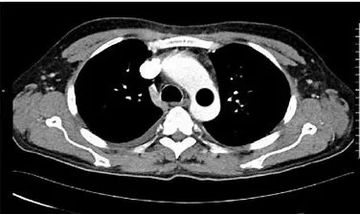

HELICAL ACQUISITION

SERIES 1: AXIAL GE:3.75X3.75 SIEMENS: 3X3 SOFT TISSUE

SERIES 2: AXIAL GE:3.75X3.75 SIEMENS: 3X3 BONE WINDOW

SERIES 3: AXIAL THINS GE:0.625X0.625 SIEMENS: 0.75X0.7

SERIES 4: CORONAL SOFT TISSUE 2X2

SERIES 5: SAGITTAL SOFT TISSUE 2X2